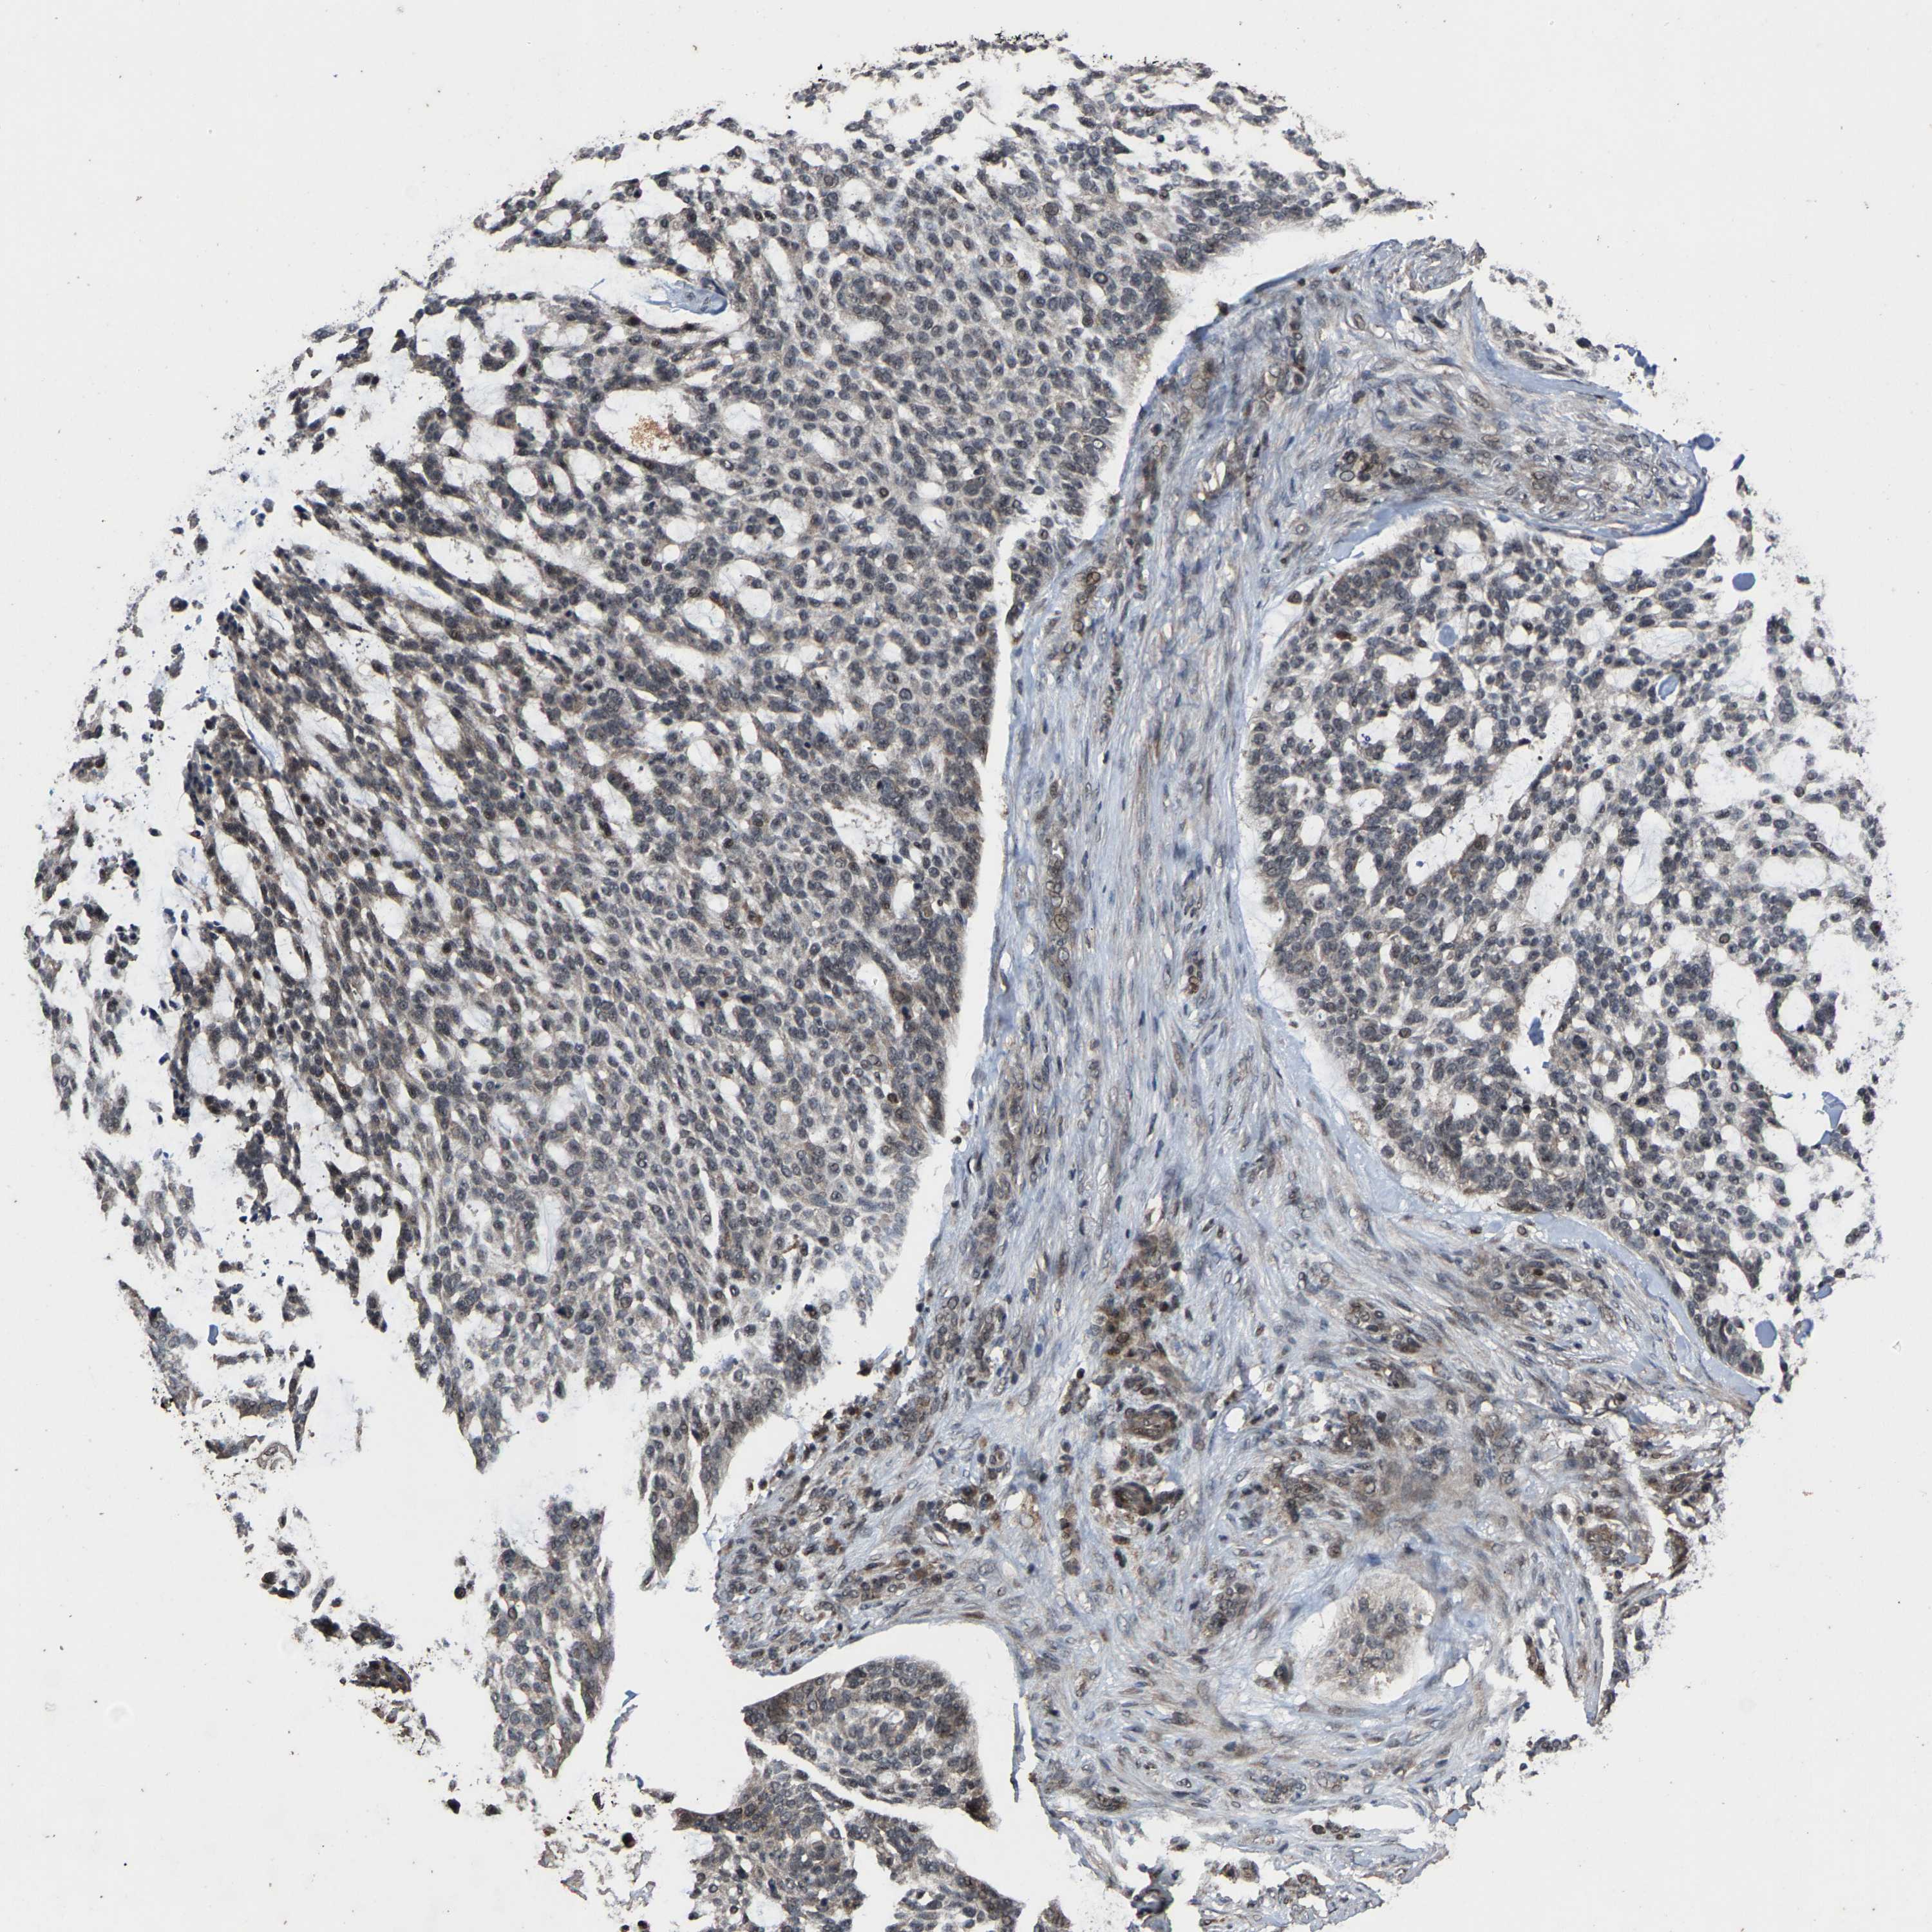

Basal cell and squamous cell cancer

SKIN CANCER - Protein expressioni

A mouse-over function shows sample information and annotation data. Click on an image to view it in a full screen mode. Samples can be filtered based on level of antibody staining by selecting one or several of the following categories: high, medium, low and not detected. The assay and annotation is described here.

Antibody stainingi

Antibody staining in the annotated cell types in the current human tissue is reported as not detected, low, medium, or high, based on conventional immunohistochemistry profiling in selected tissues. This score is based on the combination of the staining intensity and fraction of stained cells.

Each image is clickable and will lead to virtual microscopy that enables deeper exploration of all samples and also displays staining intensity scores, fraction scores and subcellular localization as well as patient and tissue information for each sample.

Antibody HPA020960

Antibody HPA020965

Staining

High

Medium

Low

Not detected

Intensity

Strong

Moderate

Weak

Negative

Quantity

>75%

75%-25%

<25%

None

Location

Nuclear

Cytoplasmic/membranous

Cytoplasmic/membranous,nuclear

Basal cell carcinoma

Squamous cell carcinoma, NOS

Squamous cell carcinoma, metastatic, NOS